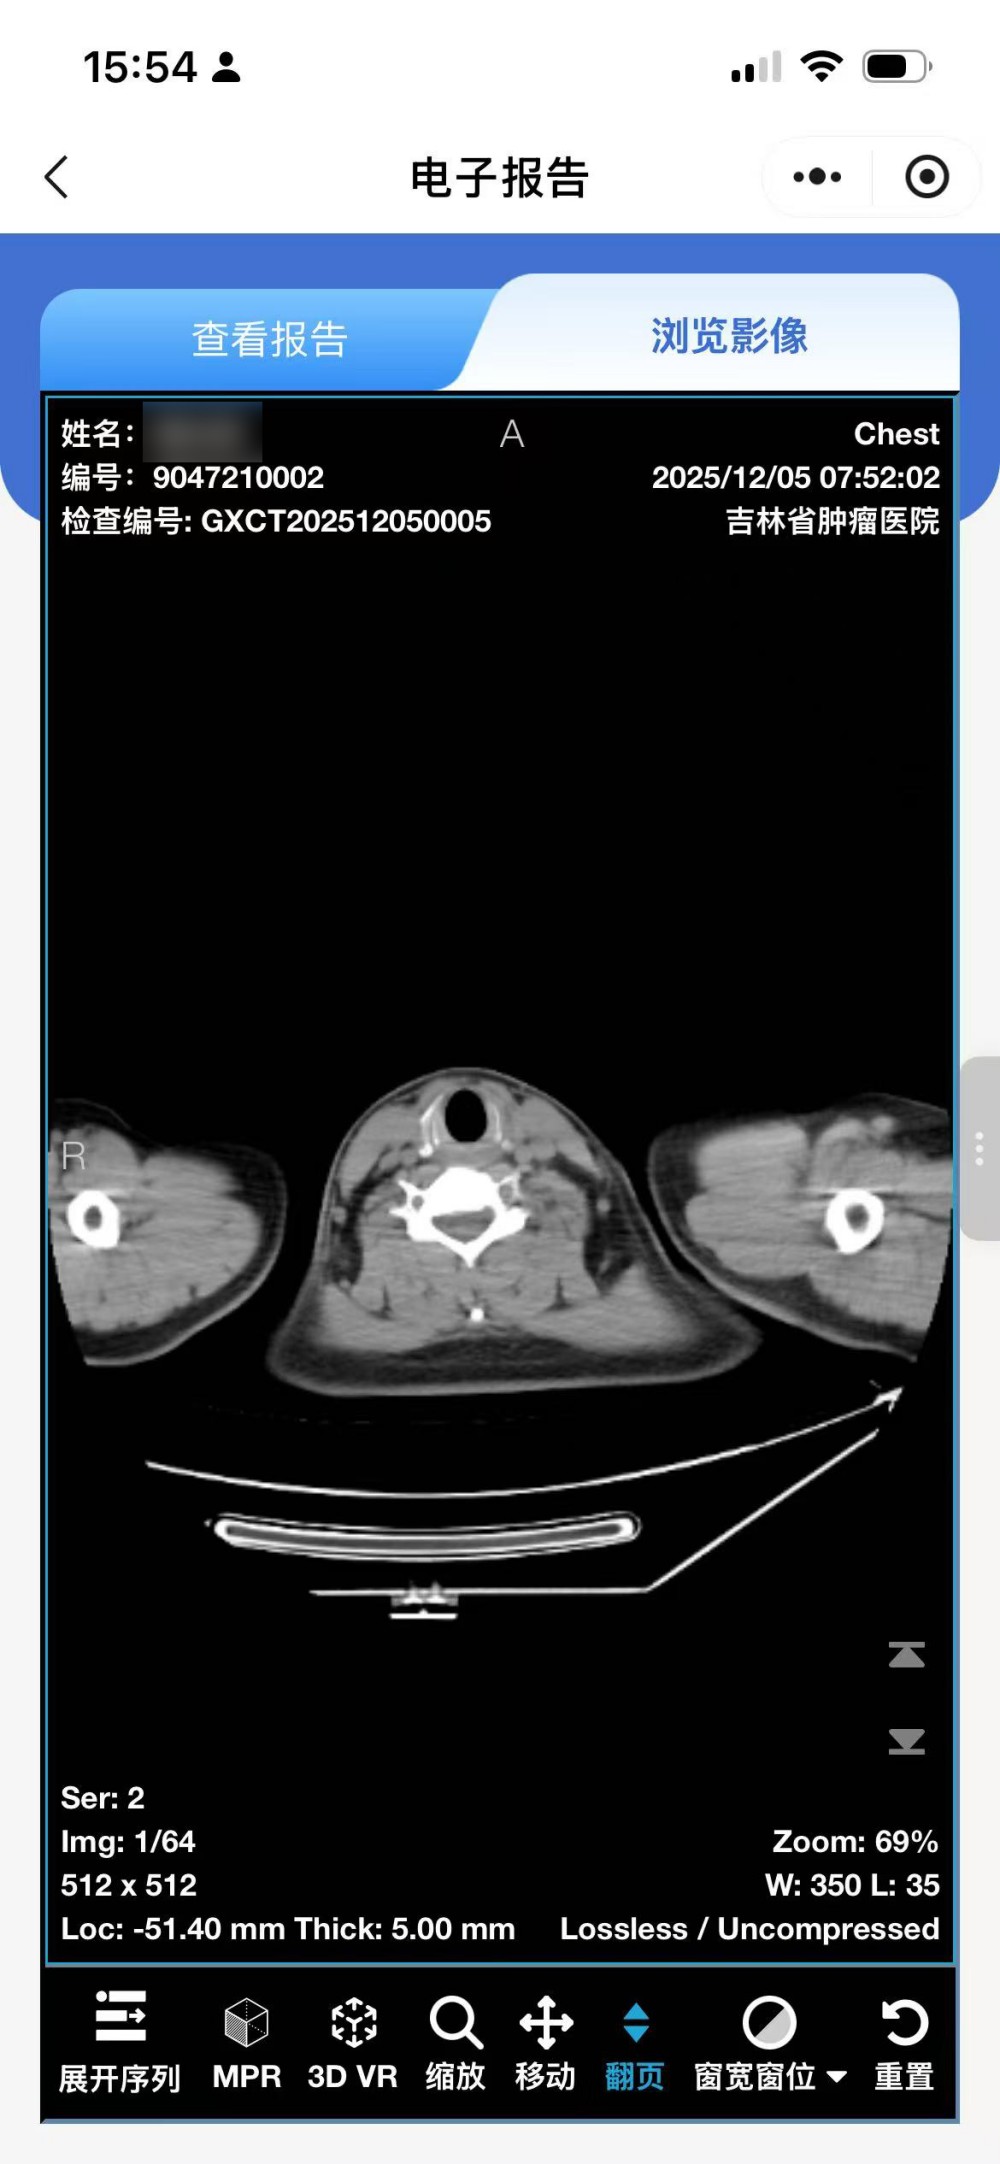

• 点击查看报告:阅读检查所见、检查印象等完整文字报告

• 点击浏览影像:查看全套影像序列,可逐张浏览具体影像图